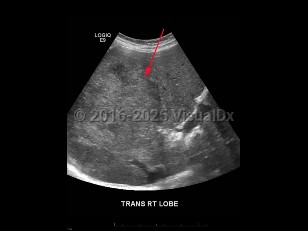

The Barcelona Clinic Liver Cancer algorithm is widely used for HCC staging:

- Very early stage (0): Solitary nodules ≤ 2 cm. Treatment includes ablation or resection.

- Early stage (A): Solitary nodule > 2 cm OR 2-3 nodules all ≤ 3 cm. Treatment options include resection, transplantation, or ablation.

- Intermediate stage (B): > 3 nodules OR ≥ 2 nodules if any are > 3 cm. Treat with chemo-embolization.

- Advanced stage (C): Macrovascular invasion OR extrahepatic spread. Treat with systemic therapies.

- Terminal stage (D): End-stage liver function. Nontransplantable HCC. Supportive care.